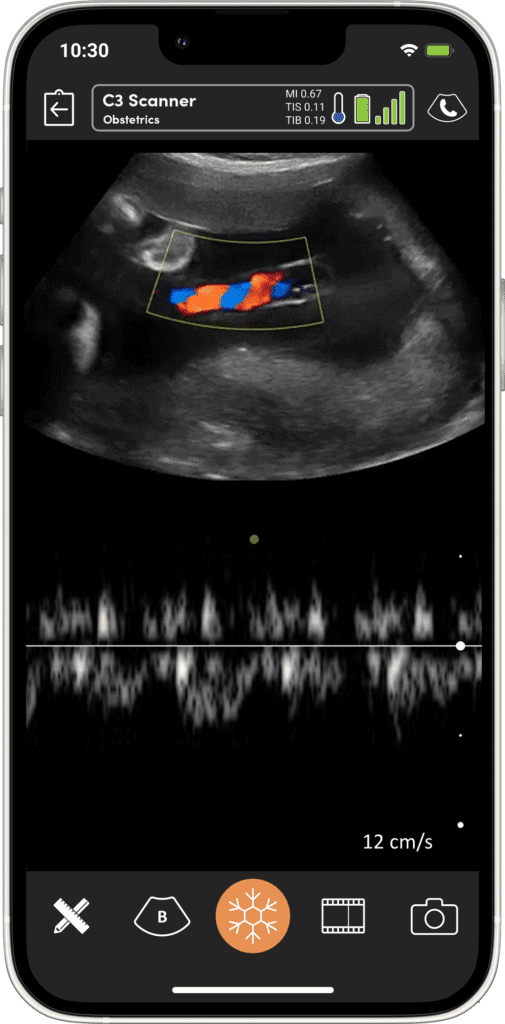

Imagerie Obstétricale Optimisée

I feel more confident with my ultrasound exams since I’ve started using OB AI. I love how the AI makes the app light up when things are perfectly lined up – I can see this really helping both seasoned clinicians and those who are starting their ultrasound journey.